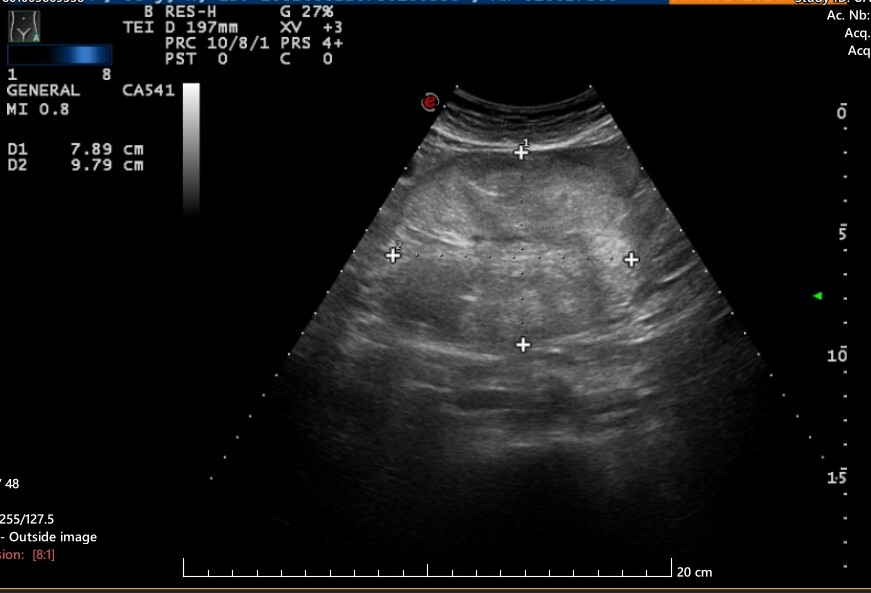

I had an ultrasound of the urinary tract last year and the liver and kidneys. on the scan an ‘incidental’ well defined 9cm hypoechoic ‘mass’ showed up on the final report with minimal vascularity on doppler interrogation at the central abdomen (above umbilicus region).

A week later I had a Abdomen CT Scan with contrast and the final report of that was that there was no abnormality found in the central abdomen and that the ultrasound finding was probably an artefact of the ultrasound imaging - for that reason they will not send me for a follow up with either ultrasound/CT or mri again because they are of the mindset that it was just an artefact and that was that and that there is nothing there even though i am still getting abdomen pains, in that area (just above umbilical cord area) - I cannot also get my head around how something so large at 9cm with a well defined edge and vascularity can be put down to an artefact.

Other investigations I am doing on the internet is pointing to suggests there is something showing up and that it is a mesenteric or retroperitoneal mass when I have sent images of the mass outlined on the ultrasound , and CT slides - what are the changes that maybe the CT radiographer has missed it on the CT slides? - at the moment the doctors have taken the decision that the CT radiographer result is final and that nothing is found and does not warrant another scan.